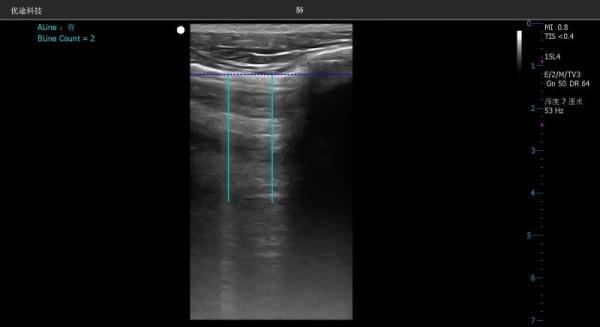

为应对新冠肺炎疫情,我校生命学院吴哲教授团队近日紧急研发了有针对性的人工智能超声图像识别技术,能够自动实时高亮显示肺部损伤,输出满足专家指南要求的信息。

吴哲教授团队进而与成都优途科技有限公司合作,把算法集成到微型超声设备上,让病患无须离开病床就可以接受检查。在肺脏模式下,胸膜线和肺泡间质综合征所造成的特殊信号(术语叫做“B线”)都会被自动识别,自动高亮显示,护士都可以进行操作。

目前,该技术正在电子科技大学医学院附属肿瘤医院超声医学中心试用,对胸膜及肺泡粘液改变形成的B线自动识别,有利于准确诊断和随访观察,减少与患者的接触时间和感染风险,而且更有助于重症医生操作,远程超声专家会诊,做出更加精准诊断。超声医学中心卢漫教授希望该技术能早日应用于抗疫一线,为战胜疫情做出一定贡献。